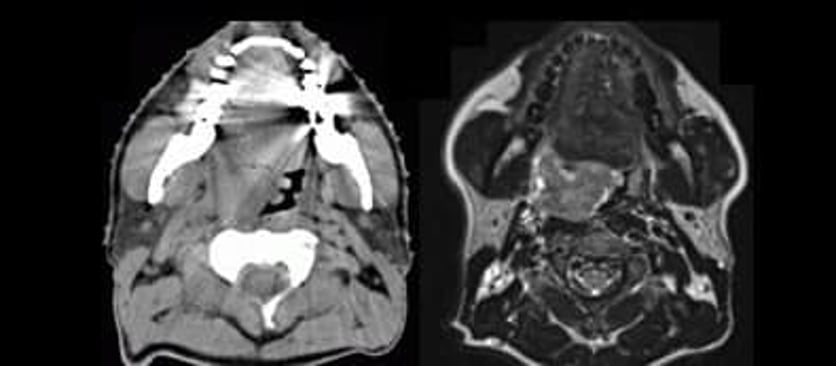

Till vänster röntgenbild med datortomografi (DT) i höjd med munhålan, till höger motsvarande bild av samma patient med magnetresonanstomografi, MRI, med tydligt förbättrad mjukdelskontrast.